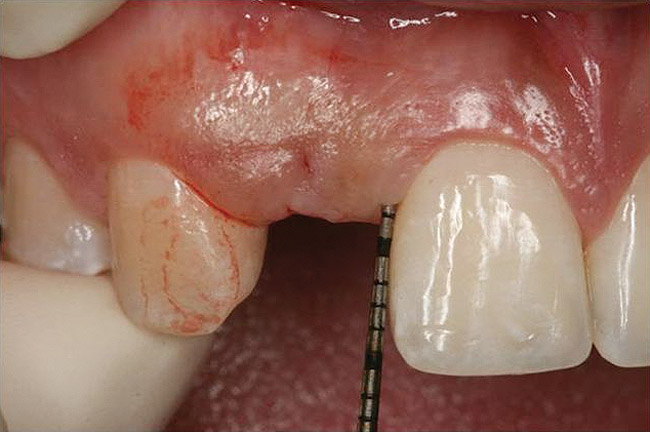

Dental implant treatment planning must focus on the architecture of the bound edentulous space. This may be divided into two separate areas of concern. As mentioned above, one is the condition of the adjacent teeth and, in particular, the level of connective tissue attachment that determines the ultimate location of papilla at the single-implant crown (Figure 10 and Figure 11). The other is the condition of the alveolus within the bound edentulous space. The extent of resorption in the vertical and horizontal direction must be considered (Figure 12). There exist several classification systems for this (eg, Seibert, Allen) that identify the presence or extent of alveolar and horizontal alveolar bone deficiency. Pragmatically, clinical resolution requires that the position of the planned implant crown be identified in the context of the alveolar bone (discussed below).

Figure 10 Clinical examination of the bound edentulous space: Measurement of the distal (Fig 10) and mesial (Fig 11) interproximal tissue height using a periodontal probe supplements data obtained from the periapical radiograph. Estimation of the buccal t

Figure 10

Figure 11 Clinical examination of the bound edentulous space: Measurement of the distal (Fig 10) and mesial (Fig 11) interproximal tissue height using a periodontal probe supplements data obtained from the periapical radiograph. Estimation of the buccal t

Figure 11

Figure 12 Clinical examination of the bound edentulous space: Measurement of the distal (Fig 10) and mesial (Fig 11) interproximal tissue height using a periodontal probe supplements data obtained from the periapical radiograph. Estimation of the buccal t

Figure 12